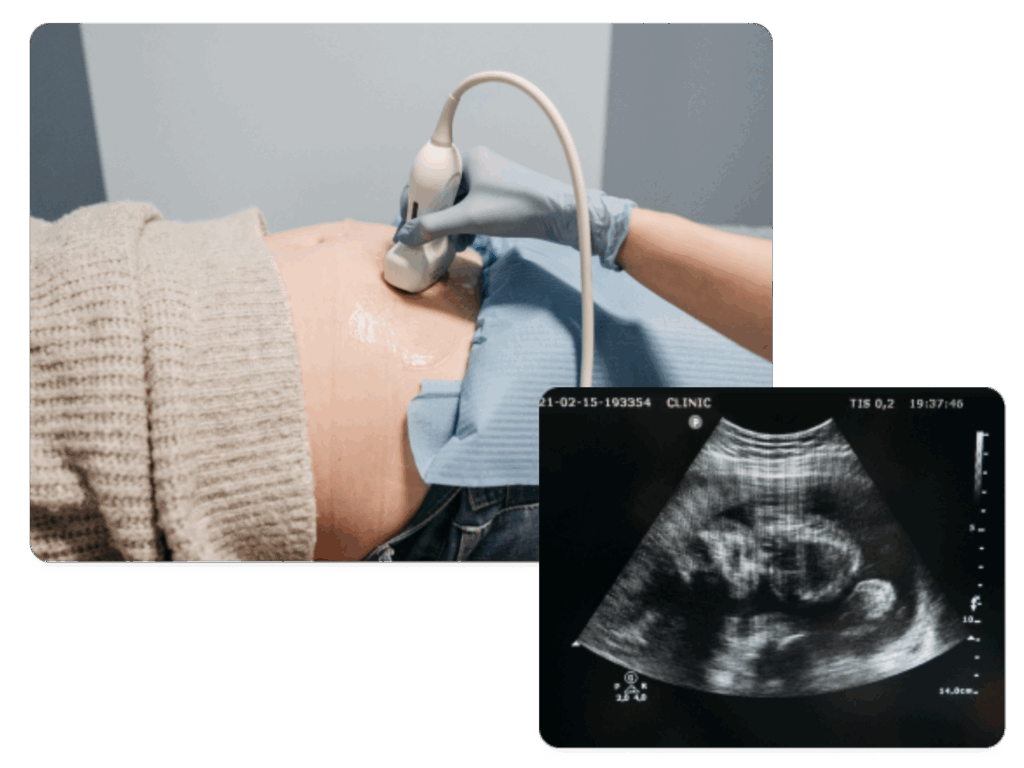

Badania prenatalne pozwalają ocenić rozwój dziecka i wykryć ewentualne nieprawidłowości już we wczesnym etapie ciąży. W Femme – Art wykonujemy nieinwazyjne testy (PAPP-A, NIFTY) oraz USG genetyczne w I trymestrze, a także USG II i III trymestru . Dzięki temu możesz świadomie i spokojnie przygotować się na przyjście dziecka.

Oferujemy pełny zakres badań prenatalnych: testy biochemiczne, genetyczne oraz specjalistyczne USG.

Pierwsze USG, które ma na celu wykrycie zwiększonego ryzyka wystąpienia wady genetycznej u dziecka, ale także ocenia inne struktury płodu to USG między 11 a 14 tygodniem ciąży.

W I trymestrze oceniamy m.in. przezierność karkową, przepływy żylne i obecność kości nosowych. Stosujemy wyłącznie sprawdzone, nieinwazyjne metody, które zapewniają wysoką czułość i bezpieczeństwo dla mamy i dziecka.

Okres pomiędzy 19 a 22 tygodniem ciąży to właściwy moment na drugie obowiązkowe badanie USG okresu prenatalnego. Ponieważ jest to USG przypadające mniej więcej na połowę ciąży jest to tak zwane USG połówkowe lub inaczej: badanie prenatalne połówkowe, USG genetyczne II trymestru, USG referencyjne, USG 19-22 tygodnia, USG anatomiczne płodu.

W badaniu USG połówkowym oceniana jest cała budowa ciała dziecka oraz dokonywane są standardowe pomiary.

Okres pomiędzy 27 a 32 tygodniem ciąży to czas na obowiązkowe badanie USG, czyli badanie USG III trymestru. Badanie USG III trymestru jest zalecane do wykonania wszystkim ciężarnym. Podczas badania USG III trymestru ocenianych jest kilka parametrów, między innymi: położenie płodu, biometria ,ilość płynu owodniowego, położenie łożyska oraz przepływy naczyniowe metodą Dopplera.